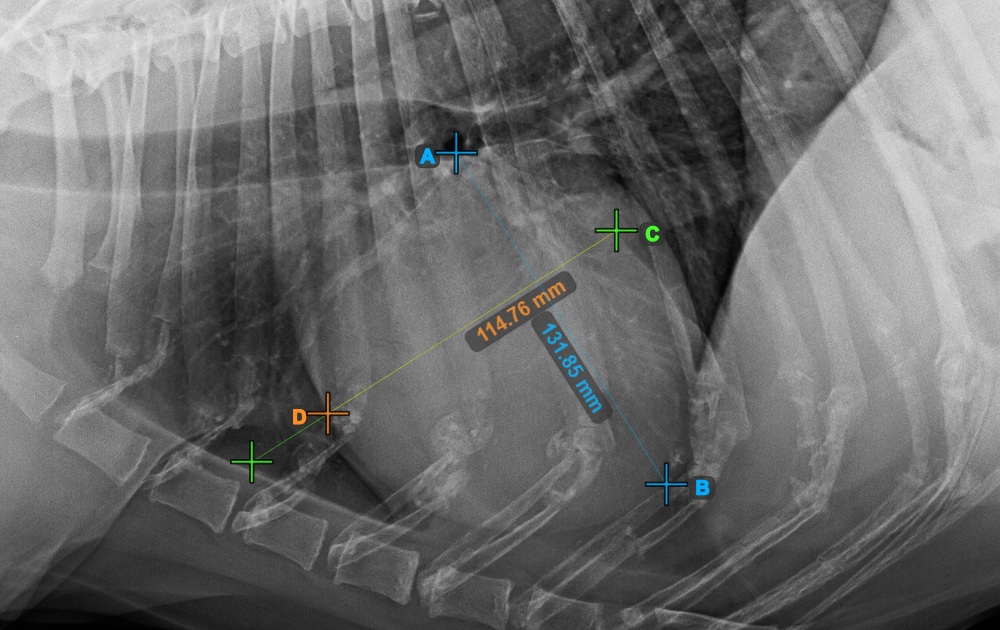

The image below represents a typical placement of the Bifurcatio tracheae point.

../../_images/image393.jpg